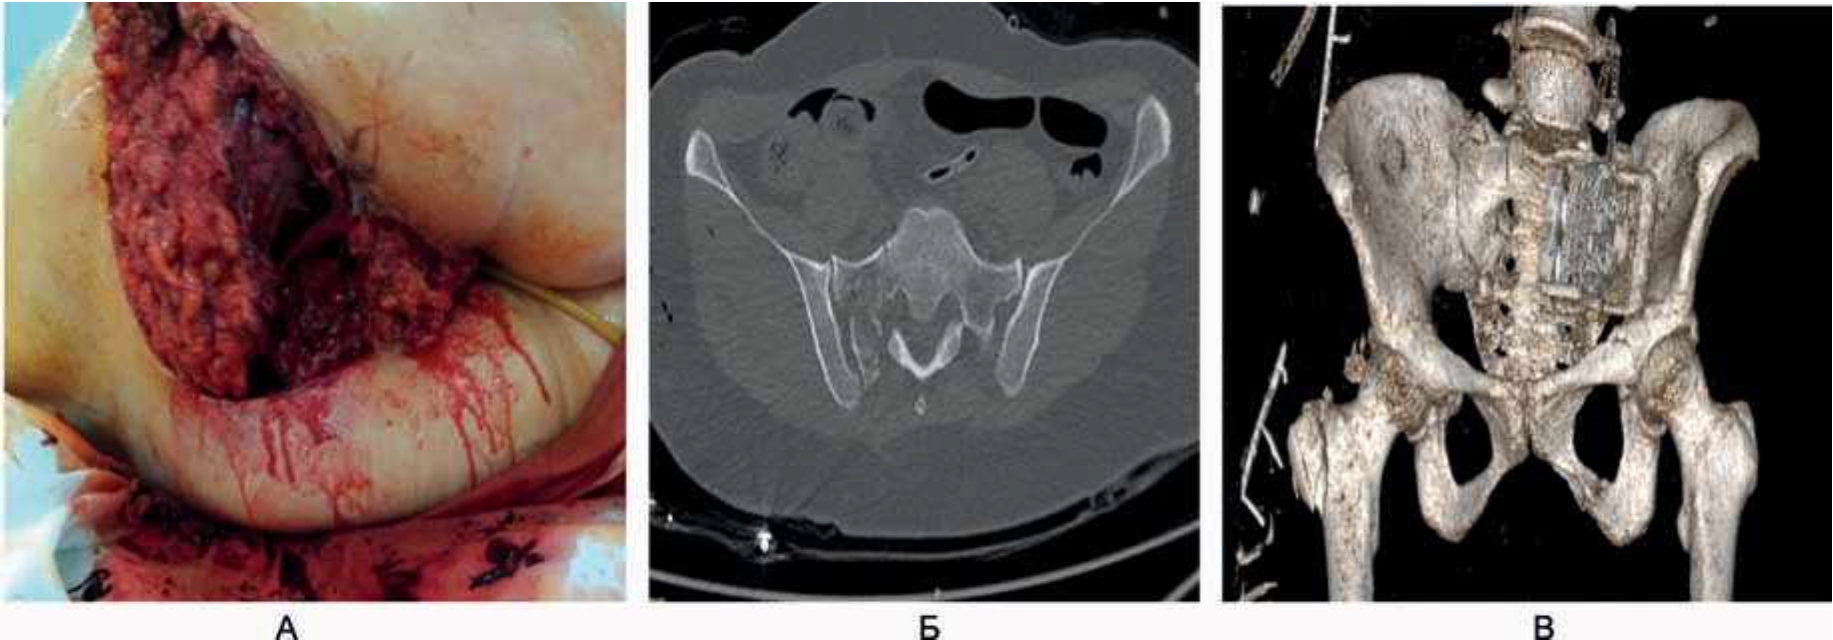

- Женщина, 34 года, поступила в приемный покой после дорожно-транспортного происшествия (ДТП). Пострадавшая была прижата к стене бампером автомобиля, двигавшегося со скоростью 20–30 км/ч. Время догоспитального этапа составило 2 ч 13 мин. Диагноз при поступлении: «Дорожно-транспортное происшествие. Тяжелая сочетанная травма головы, таза, конечностей. Закрытая черепно-мозговая травма. Закрытая ротационно-нестабильная травма таза с переломом боковой массы крестца справа, лонной и седалищной костей слева. Открытый перелом большого вертела правой бедренной кости. Обширные рваные раны правой паховой области и промежности. Обширная циркулярная отслойка кожно-жирового лоскута правого бедра, правой ягодичной области с отрывом и размозжением большой ягодичной мышцы. Обширная рвано-ушибленная рана промежности в области большой половой губы справа с переходом на наружный сфинктер и слизистую оболочку прямой кишки. Острая массивная кровопотеря тяжелой степени тяжести. Шок III степени» (рис. 4).

Рис. 4. Догоспитальный этап. Обширная циркулярная отслойка кожно-жирового лоскута правого бедра, правой ягодичной области с отрывом и размозжением большой ягодичной мышцы. Оценка площади поражения (А), компьютерная томография (Б), мультиспиральная компьютерная томография с 3D-рентгенологической реконструкцией костей таза (В).